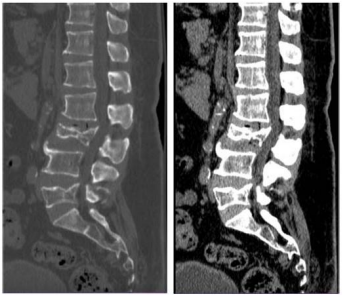

Caso clínico para responder à questão.

Um paciente de 62 anos de idade foi vítima de queda da

própria altura há cerca de três horas. Ele chegou ao

pronto-socorro queixando-se de dor lombar de moderada

intensidade.

No caso descrito, foi solicitada uma TC da coluna lombar, conforme apresentado. Esse exame mostra fratura de